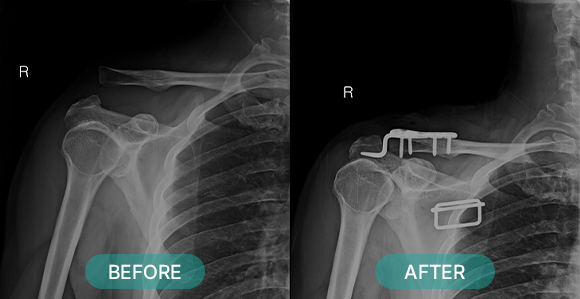

수술적 치료 방법에는 크게 관혈적 정복 과 비관혈적 정복으로 나눌 수 있습니다.

관혈적 정복이란 골절된 부위를 절개하고 뼈를 노출시켜 눈으로 직접 보면서 골절편을 정확하게 맞추는 방법으로 금속판과 나사 고정법, 핀고정법, 나사고정법, 골수 내정 고정법, 인공 관절 치환술, 외고정 기구 고정법 등등 여러 방식이 있습니다.

비관혈적 정복이란 골절 부위를 노출시키지 않고 골절편을 맞춘 이후 고정을 시행하는 방법입니다.